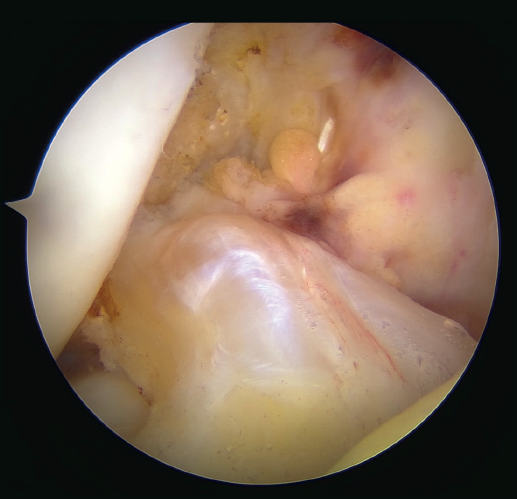

The patient is placed in the supine position and the leg is draped and prepared for knee arthroscopy at the surgeon's discretion, as if an ACL plasty were to be performed. The anterolateral and anteromedial portals are established as usual, and the joint is explored. On exploring the central compartment, it should be confirmed by direct vision and also palpation that the lesion is proximal and that the tissue quality is good; if the tissue is friable and tears easily, repair is not indicated. If the ACL remnant is attached to the PCL, it must be dissected so that the ACL is free and can be manipulated to its insertion site. A blunt shoulder arthroscopy periosteotome is best used for this, although a synoviotome, vaporizer or plasma applicator could also be used, as long as care is taken not to break or burn the tissue and render it non-viable. If there are concomitant meniscal or cartilage lesions, they should be treated earlier in order to avoid forced varus and valgus positions after the repair is completed.

After having confirmed the proximal lesion of the ACL and the good quality of the remnant ligament tissue, and having treated any accompanying injuries in the other compartments, an accessory anteromedial portal is prepared. It is important to widely resect Hoffa's fat pad to improve vision, facilitate passage of the threads, and prevent the latter from adhering to soft tissues. A cannula, ideally flexible (PassPort® from Arthrex), should be used to prevent the threads from adhering to the soft tissues, although this is not essential. The use of long cannulas, such as shoulder cannulas, is not ideal, as they extend too far outside the skin and greatly restrict use of the instruments.

Once a good view of the central compartment is obtained, the area of the femoral footprint of the ACL is prepared to leave exposed bone, and microperforations are made in the medial wall of the lateral condyle to leave a bleeding bed to favor healing of the ligament (Figure 3). These microperforations can be made using specific instruments or with the implant punch. The advantage of using the punch is that the implant insertion site can be prepared at the same time, and only one instrument is used for the entire process (Figure 4). This step can be done after the suture has been prepared in the ligament, although doing it beforehand avoids the threads from standing in the way. The ideal point for fixation is just anterior to the native ACL footprint, although if the tear is partial or corresponds to Sherman I, it can be taken to the anatomical footprint without difficulty.